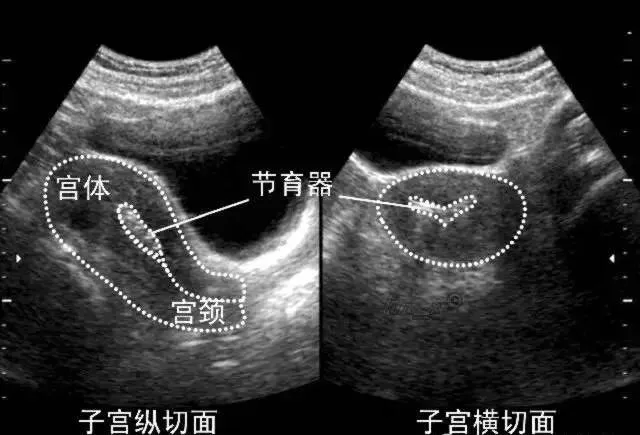

●声像图表现:宫腔内线性、圆形或三角形强回声。

●宫内节育器位置正常:节育器强回声位于宫腔中心,其周围内膜显示为低回声的晕圈。在子宫纵切面可判断宫内节育器在宫腔内的位置正常位置的宫内节育器应全部位于宫腔内,且节育器最下缘不低于宫颈内口。